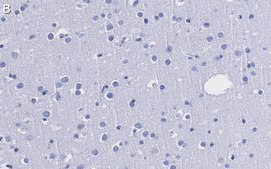

Immunohistochemistry (Paraffin) Analysis: A 1:1,000 dilution from a representative lot detected Cereblon (CRBN) in human cerebral cortex tissue sections.